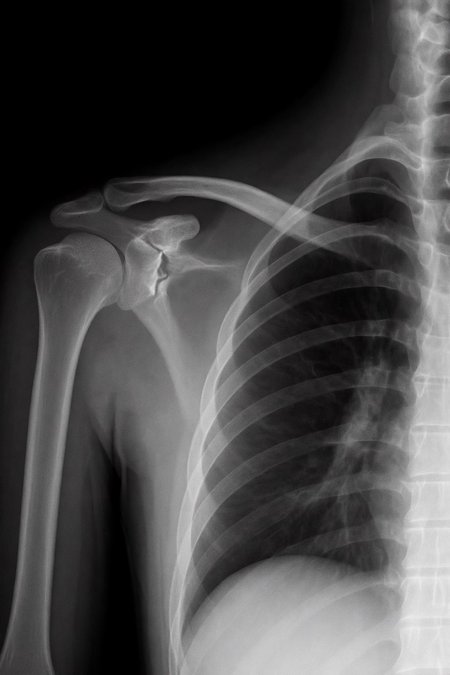

Can a model like Flux Kontext, designed for editing art and photography, be used to work with medical images, for example, with something 'as simple' as red-marking fractures?

The quick answer: it does do something interesting, but it over-scores and is far from reliable as a medical tool. It's a prototype to play with the idea, nothing more.

Good for

AI prototypes and tests on medical imaging.

Eye-catching visualizations of "suspicious" areas in X-rays (experimental and creative art, here's an exotic tool xD)

Didactic/experimental material to play with sensitivity vs false positives.

Not good for:

Diagnose nothing serious.

Replacing a doctor, not even close!